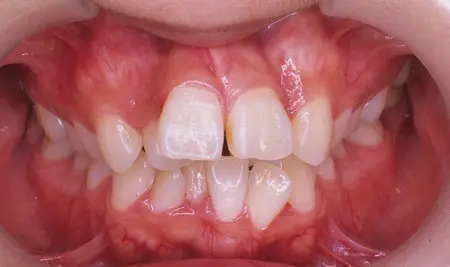

2024.08.1720代女性「出っ歯と歯のガタガタが気になる」叢生を伴う上顎前突症をワイヤー矯正で治療した症例